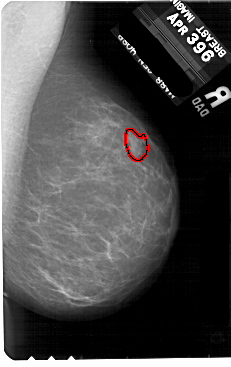

A_1886_1.LEFT_CC

RIGHT_CC LINES 5491 PIXELS_PER_LINE 3211 BITS_PER_PIXEL 12 RESOLUTION 43.5 OVERLAY

FILE: A_1886_1.RIGHT_CC.OVERLAY

TOTAL_ABNORMALITIES 1

ABNORMALITY 1

LESION_TYPE MASS SHAPE IRREGULAR MARGINS ILL_DEFINED

ASSESSMENT 4

SUBTLETY 3

PATHOLOGY BENIGN

TOTAL_OUTLINES 1

BOUNDARY